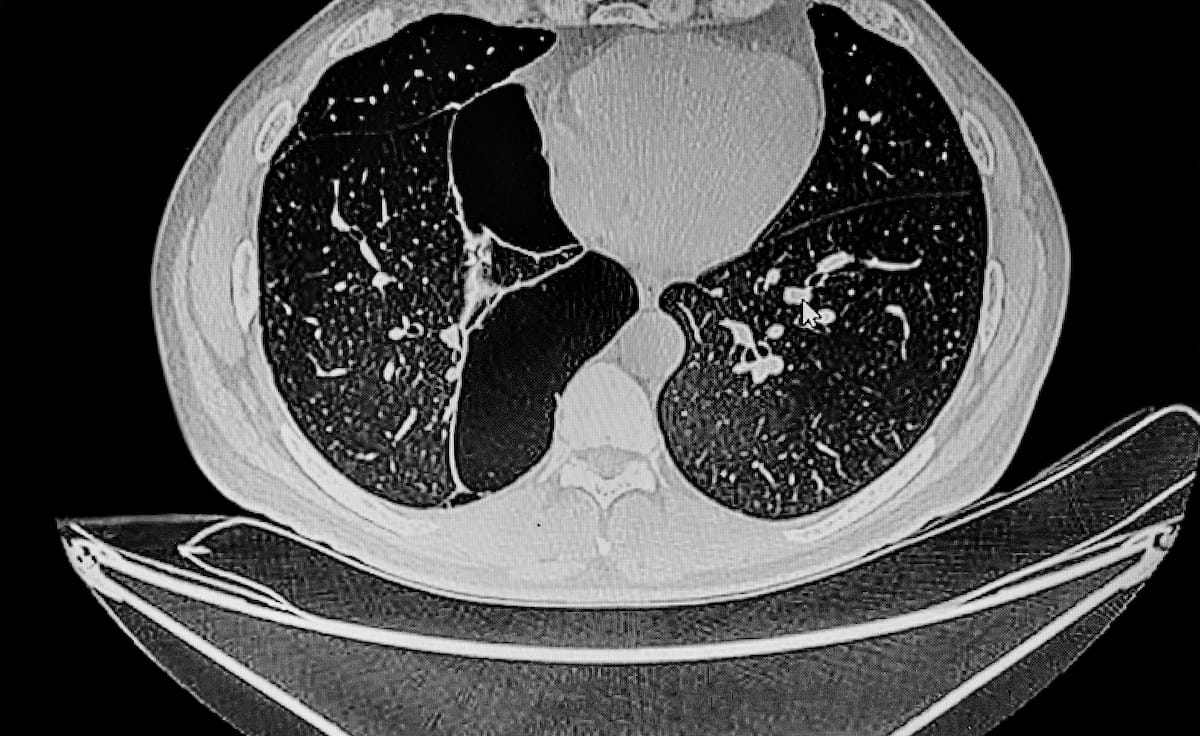

In a review of patient data from 42 countries, researchers found that standardized typical findings on computed tomography (CT) for COVID-19 had a pooled sensitivity rate of 70 percent and a pooled specificity rate of 90 percent.